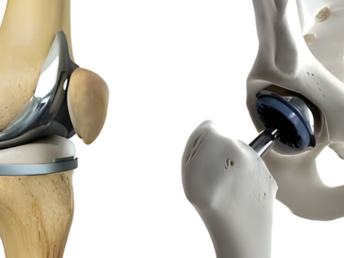

Joint Replacement

01. Orthopedic surgeries including arthroscopy and joint replacements.

Advanced surgical procedures to treat joint issues, restore function, and enhance movement through minimally invasive and replacement techniques.